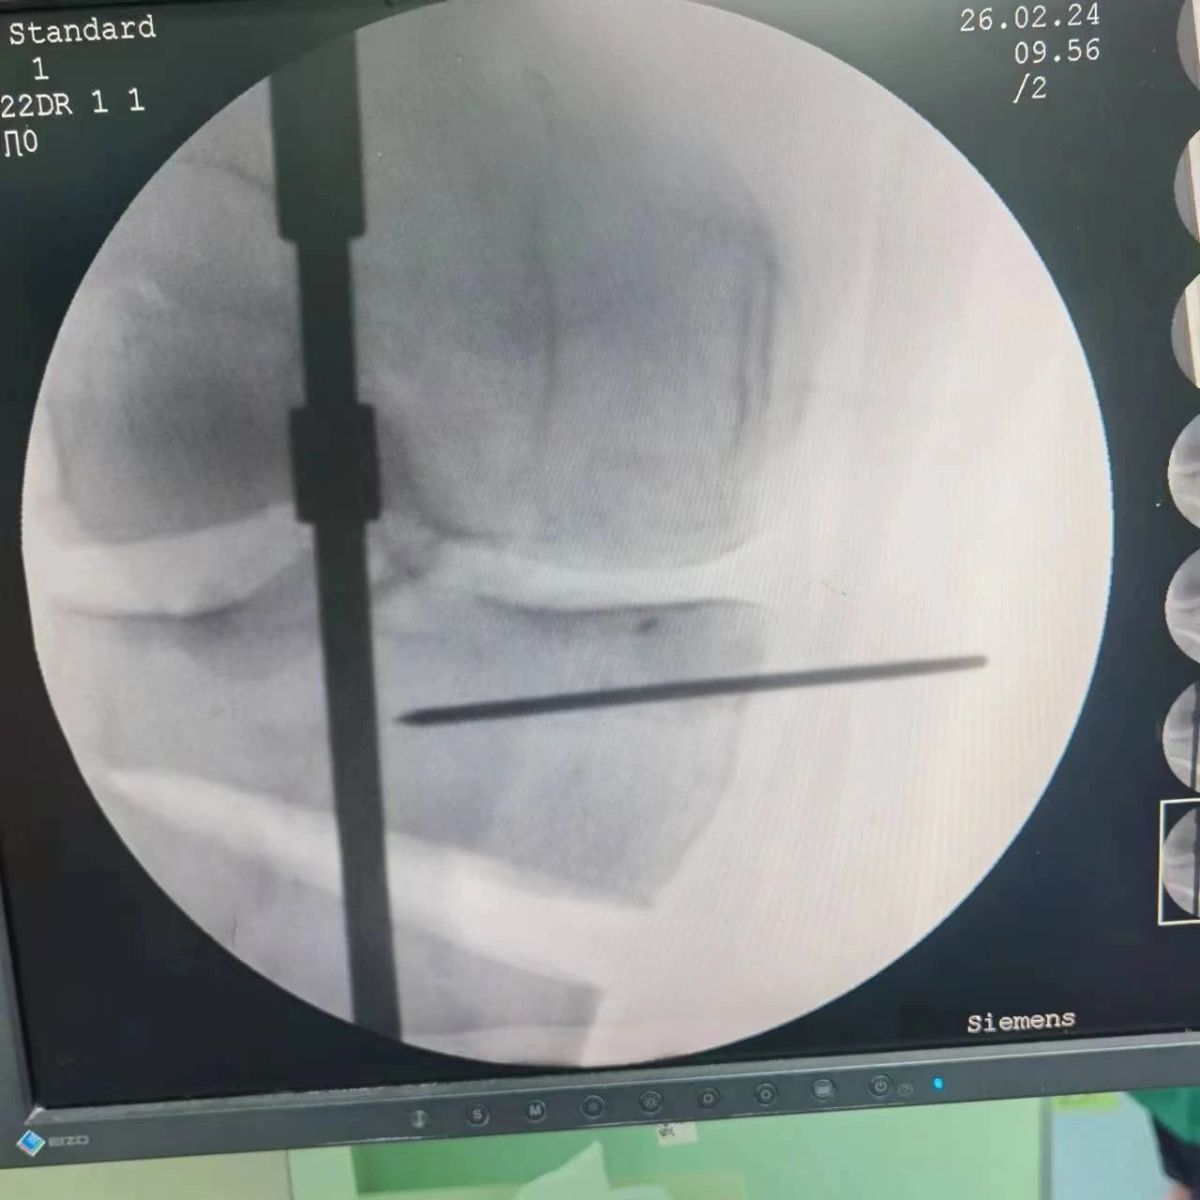

2月26日,漯河市骨科醫(yī)院(漯河醫(yī)專二附院、漯河市立醫(yī)院)膝關(guān)節(jié)外科、運(yùn)動(dòng)損傷科(骨六科)在保膝治療方面取得了新的突破,李付彬主任帶領(lǐng)岳龍等團(tuán)隊(duì)醫(yī)師,順利完成“計(jì)算機(jī)精準(zhǔn)術(shù)前規(guī)劃聯(lián)合3D打印截骨導(dǎo)板輔助脛骨高位截骨治療膝關(guān)節(jié)骨性關(guān)節(jié)炎”的手術(shù),這在漯河市尚屬首例!

李付彬主任團(tuán)隊(duì)通過精準(zhǔn)術(shù)前規(guī)劃,設(shè)計(jì)目標(biāo)力線及調(diào)整撐開角度,轉(zhuǎn)化成需要撐開的高度,最終設(shè)計(jì)出同等高度的填充塊,術(shù)中驗(yàn)證力線調(diào)整與術(shù)前規(guī)劃完全一致!

鋼板位置、螺釘位置及長度均可通過術(shù)前規(guī)劃計(jì)算,術(shù)中通過定位操作,基本與術(shù)前規(guī)劃一致,手術(shù)快速高效完成,外側(cè)合頁保留完整。無任何并發(fā)癥出現(xiàn)。術(shù)后見鋼板位置及力線糾正近乎完美!

OWHTO手術(shù)效果依賴于多個(gè)數(shù)據(jù)參數(shù),比如:截骨的入點(diǎn)、合頁位置的選擇、截骨線的深度、截骨線的方向、撐開的距離等,依托計(jì)算機(jī)術(shù)前精準(zhǔn)規(guī)劃和3D打印導(dǎo)板可輔助醫(yī)生精準(zhǔn)控制上述參數(shù),使截骨更準(zhǔn)確,真正達(dá)到精確的力線調(diào)整,減少術(shù)中透視次數(shù),縮短手術(shù)時(shí)間并降低手術(shù)風(fēng)險(xiǎn),從而使得OWHTO得到更好的應(yīng)用,造福患者。